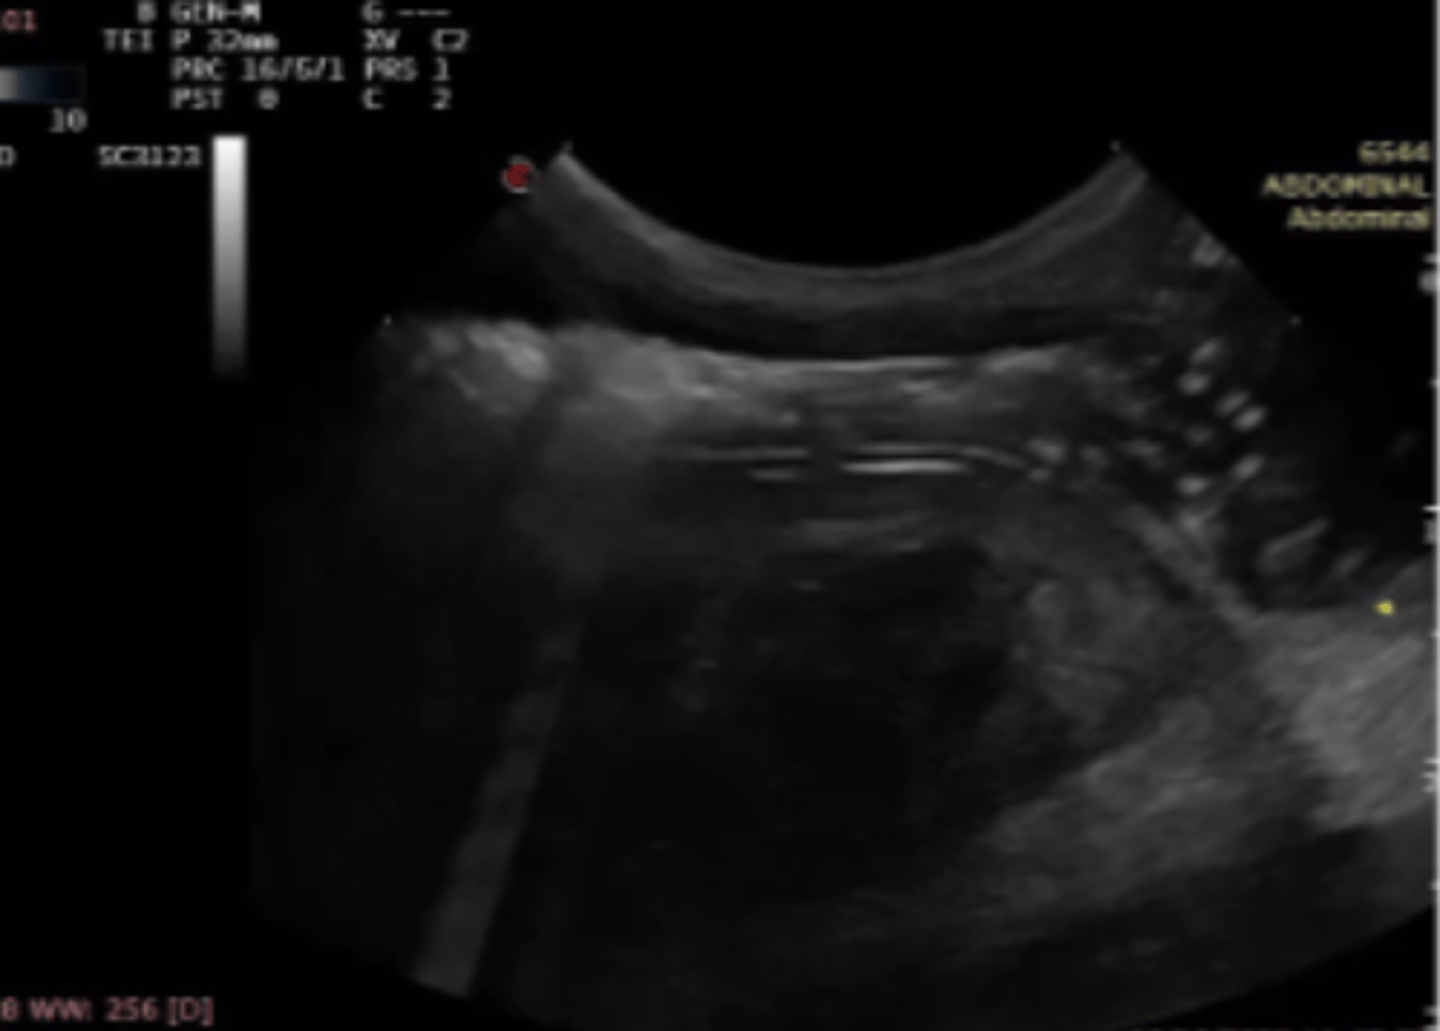

(objeto hiperecoica + sombra)

patología:

cuerpo extraño en estomago